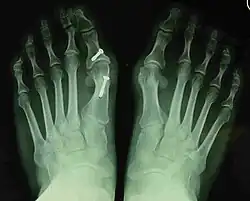

- For recurrence correction after osteotomy procedure (Fig. 8)

Late deformity recurrence can happen after osteotomy (bone-breaking) procedures because osteotomy surgeries do not specifically stabilize first metatarsal bone.